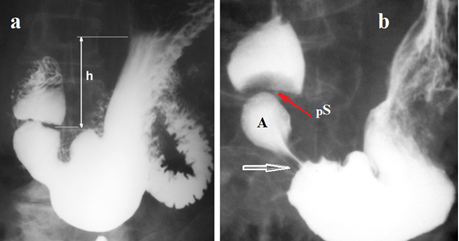

The angle of his an increase in the angle of His is considered a factor that contributes to the development of GERD. Figure 8 shows the pathogenesis of this phenomenon.

Figure 8(a-b) Radiographs of the left dome of the diaphragm of a healthy person (a) and a patient with GERD (b). (c). Scheme of the EGJ with normal LES function (red). The angle of His (aH) is acute. Large gas bubble in the stomach. (d). In GERD, the LES is shortened because the abdominal part of the LES (aLES) is not functioning. This leads to an increase in the angle of His and a decrease in the gas bubble of the stomach.

Based on manometric,38 radiological5 and histological studies,39 it has been established that the LES in GERD is shortened due to the opening of the abdominal part, which to varying degrees ceases to perform the antireflux function. As can be seen from Figure 8, shortening of the LES not only weakens its antireflux function, but also leads to an increase in the His angle. At the same time, reduces the gas bubble in the stomach. Weakness of the LES causes periodic relaxation of the LES, which is accompanied by belching. Histological studies of Chandrasoma have shown that in health the esophageal squamous epithelium transitions at the GEJ to gastric oxygentic epithelium with no intervening cardiac epithelium. The cardiac metaplasia of the squamous epithelium occurs due to exposure to gastric juice.39 This irrefutable evidence testifies that the cause of GERD is due to damage to the EGJ by hydrochloric acid. All other factors that supposedly influence the development of GERD,40 are the result of the disease, i.e., manifestations of pathogenesis. For at least 15 years, against the backdrop of pointless criticism from practical gastroenterologists, the Chandrasoma hypothesis remains valid. Moreover, it allowed us to abandon two widely common hypotheses. These are the belief that cardiac epithelium normally lines the proximal stomach, and that the GEJ is defined by the proximal limit of rugal folds.39 These two already rejected hypotheses, which were not based on scientific research, were the basis for the erroneous statement about the upward movement of the LES with shortening of the esophagus and the formation of a hiatal hernia.